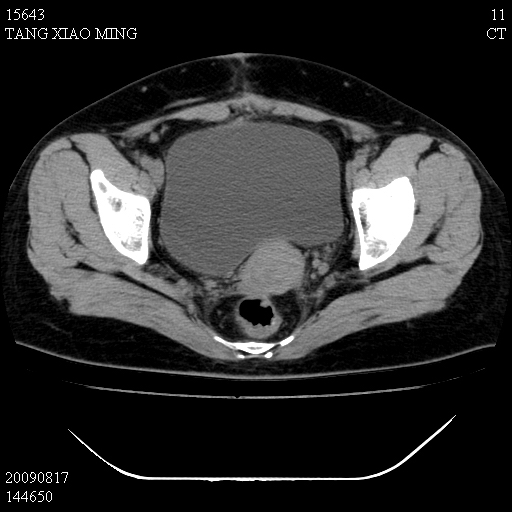

标题: CT21692:盆腔病变

女,33岁,右下腹痛2年余,既往宫外孕病史,如在我院手术,结果下周公布,

可能的诊断。1子宫内膜异位【子宫腺肌症并右卵巢巧克力囊肿】;2 右卵巢囊腺瘤。子宫肌瘤

1)考虑卵巢巧克力囊肿,不排除卵巢囊腺瘤。2)子宫肌瘤可能。

卵巢囊腺瘤,子宫肌瘤,直肠壁厚,不除外占位.